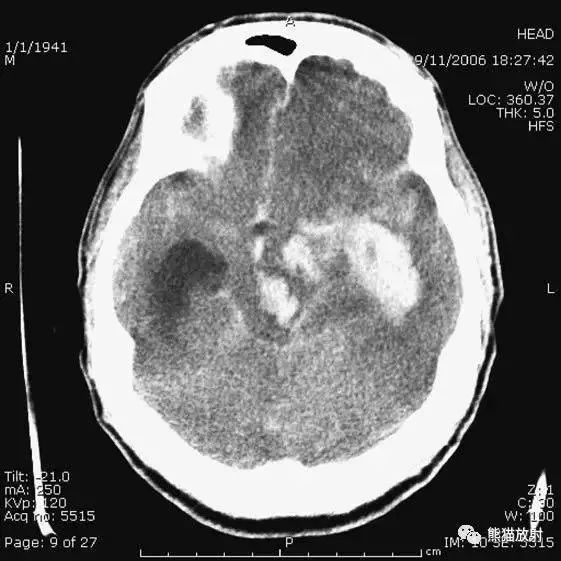

5、高血压性脑出血

高血压性脑出血:自发性出血;

继发于长期高血压及慢性血管病;

常见于基底节区、丘脑、脑桥、小脑。

A:占位效应,相邻脑沟、脑池消失;

F:脑出血破入四脑室。

▲钩回疝:

是当代偿机制不能适应占位性病变时的结果。

基底节区大量高血压性脑出血,破入脑室及蛛网膜下腔,周围水肿,脑干周围空间消失;脑干出血、脑积水。